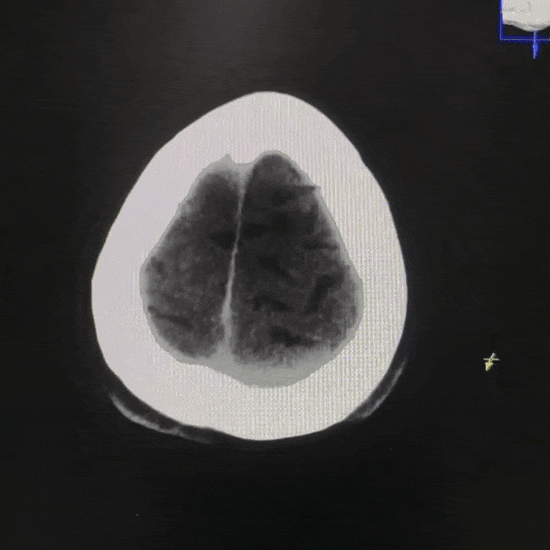

术后第一日复查 CT

术后 24 小时左右复查 CT:原先左侧额叶前部的显著高密度影已消失,左侧侧裂池后部和额叶后部高密度影较前明显吸收,残留少许稍高密度影。